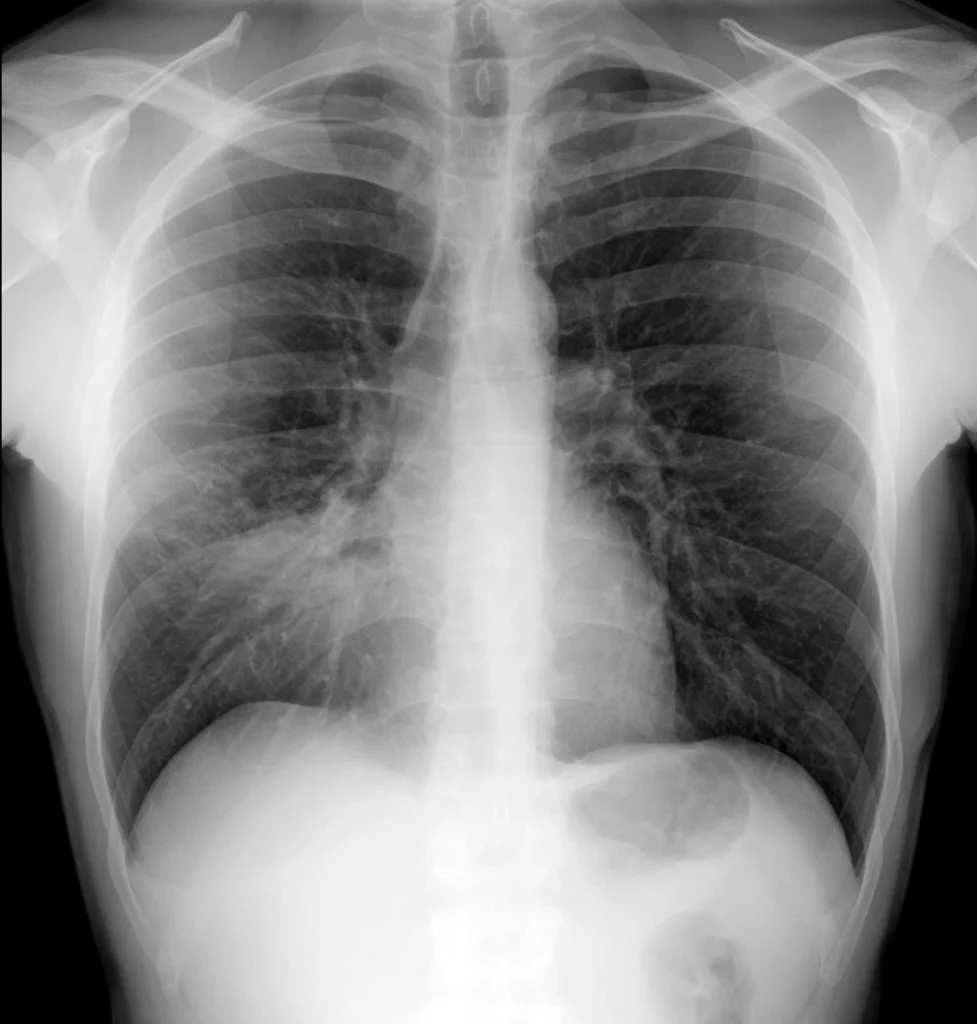

Rx de tórax PA. Consolidación en el tercio inferior del pulmón derecho, en localización paracardiaca. El borde del corazón no se identifica claramente. El signo de la silueta es positivo.

En la proyección PA, se observa una consolidación en el tercio inferior del pulmón derecho, que borra el contorno del corazón, el signo de silueta es positivo. En la proyección lateral se confirma la localización de la consolidación en el lóbulo medio, proyectada sobre la silueta cardíaca.